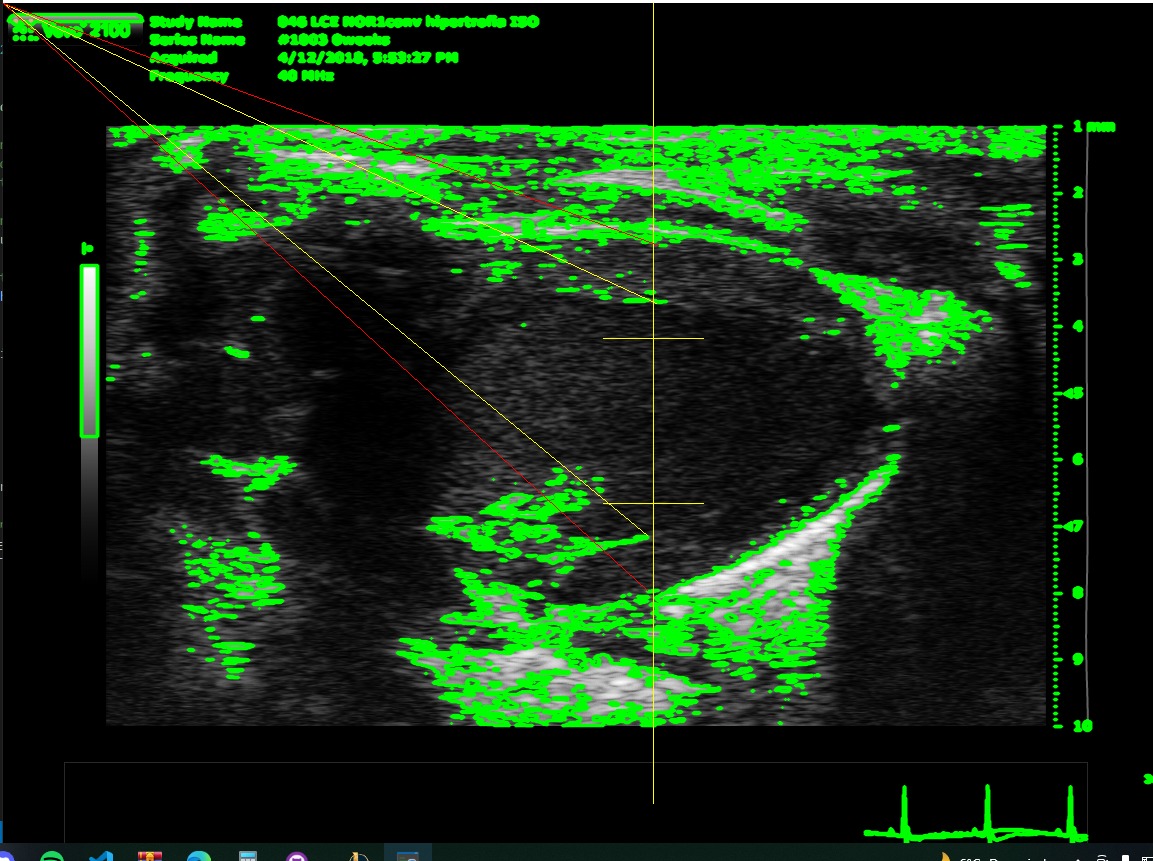

Its a CLI's program where have to give a psla and sax dicom files path. Then gets some variables from the files to throw some conclusions (if it's a healthy heart or not) and also it save it as excel file.

We built it as a python project with its virtual environment with the requirements needed, also needs a special program called Theseract that it is a optical character recognition open source to get the BPM from the files, the rest of the needed parameters are calculed using opencv mainly.

The most significative challenge that the team ran into consisted in the identification of the contourns of the image. Differenciating between the underside and the outer layer of the blood vessel ended up being an arduous task

Since distinguishing between the outer and inner layer was one of the most challenging and troublesome problem that the team integrants had to face, it's one of the most relevant acomplishments. It should also be noted that finding an external program that could be included in the project to easen the identification of text was also remarkable